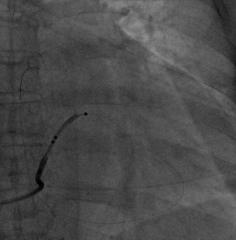

6225i球囊造影可见轻微夹层,远端未显影

6250VIS鞘管直接造影可见分支显示良好

AP

LAO